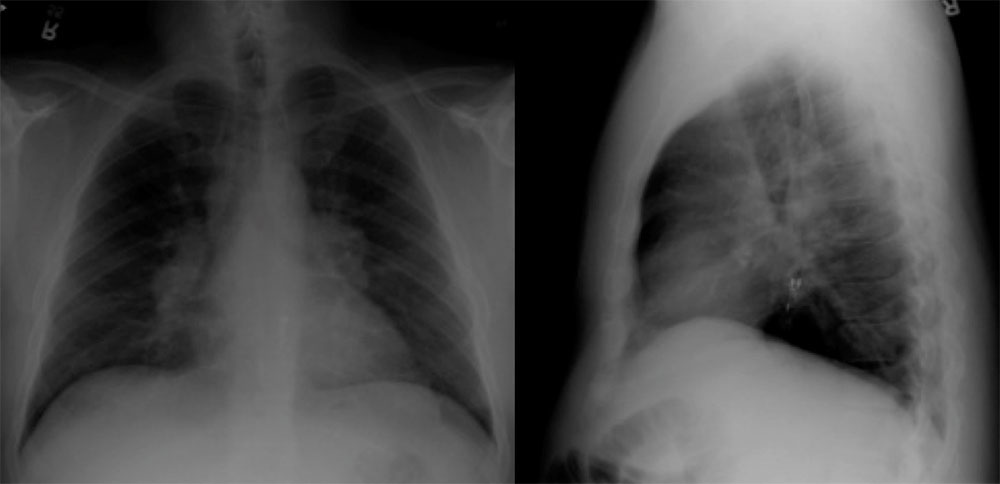

Case 10  Chest radiograph on a 48 year old man shows:

Case 10  Chest radiograph on a 48 year old man shows:

Wireless capsule pH monitoring device